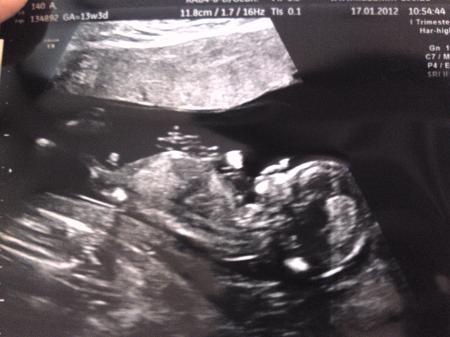

schau mal auf dem rechten bild, da wo die beine anfangen, zeigt ein schniepel nach oben :))) hab nochmal das bild in größer mit rangehangen... Lg

Bild zu

der kleine schnipel da?? ha jetzt konnte cih es auch sehen es ist doch nicht hopfen und malz verloren bei mir